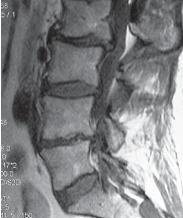

Чтобы вы лучше понимали, как выглядит позвоночник когда в позвоночном сегменте уже нет диска и происходят вышеупомянутые процессы фибротизации и васкуляризации (относящиеся к последней стадии развития дегенеративно-дистрофического процесса), приведу ещё один снимок пациента после многократных хирургических вмешательств.

На МРТ № 102 хорошо видно, как после многократных хирургических вмешательств образуется множество послеоперационных рубцов, спаек и других проблем в позвоночнике. То есть, созданы все условия для фибротизации (перерождения ткани диска, образования фиброзных волокон) и васкуляризации (лат. vas — сосуд; формирования новых капилляров, в данном случае при процессе сращивания костной ткани). Всё это способствует сращиванию двух смежных тел позвонков, лишённых диска. В свою очередь это исключает подвижность в данном сегменте, приводит к стенозу фораминальных отверстий (как вы помните, это отверстия, через которые проходят нервные корешки и сосуды). Вдобавок ко всему, послеоперационные спайки и рубцы в спинномозговом канале могут способствовать развитию воспалительных процессов, о которых уже упоминалось выше. Нарушение функциональной способности данного позвоночного сегмента ведёт к ещё большим биомеханическим нарушениям в позвоночнике, соответственно частичной утрате его рессорных свойств, а следовательно, значительному снижению сопротивляемости к разнообразным вертикальным нагрузкам.